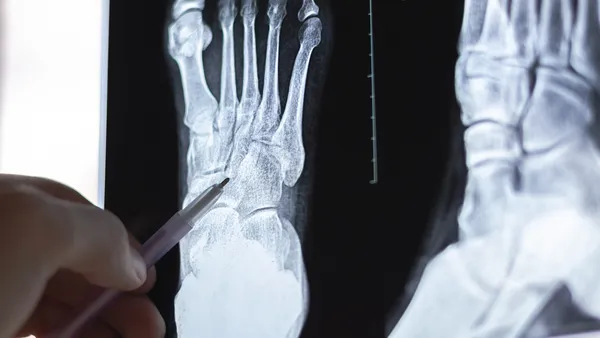

Stressfracturen

Veel lopen in schoenen zonder goede ondersteuning kan de botten en gewrichten extra belasten en leiden tot stressfracturen. Dit zijn kleine scheurtjes in de botten die vaak veel pijn veroorzaken.